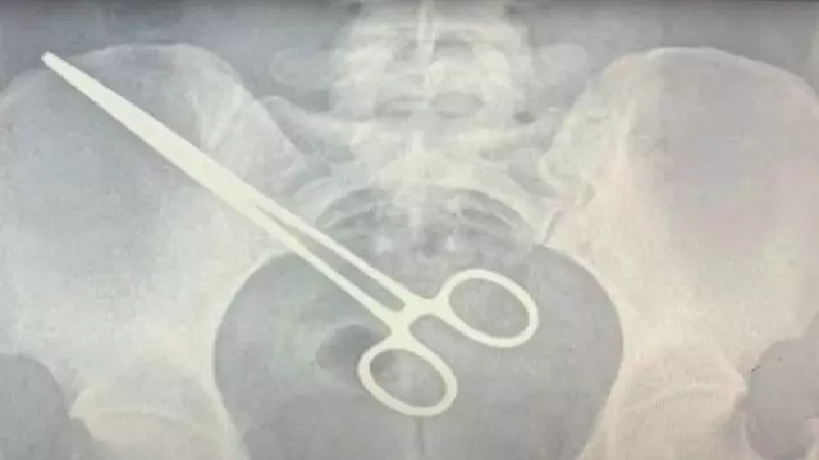

A imagem do raio-x mostra a pinça cirúrgica alojada no corpo da paciente. Com o objeto esquecido, uma nova cirurgia foi feita para a retirada do item, além de dez centímetros do intestino, ferido pela pinça. Por conta do erro médico, Jade procurou um advogado e pretende entrar com uma ação na Justiça.